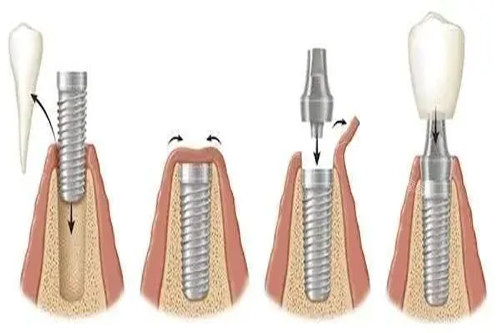

All-on-4 方案是一种较高的全口种植技术,需要植入 4 颗种植体就能支撑起一整排牙齿。其中,两颗前牙区种植体垂直植入,后牙区两颗种植体呈倾斜角度植入。这种设计巧妙利用力学原理,在骨量不足的情况下,可避开上颌窦、下颌神经管等危险区域,减少植骨需求,同时为牙桥提供稳定支撑,实现即刻负重,大大缩短患者缺牙时间,术后短时间内就能修复部分咀嚼功能。

伊诺全口 All-on-4 方案中,4 颗种植体费用占总价的较大比重。伊诺种植体采用四级纯钛材质,具备良好的生物相容性与机械强度,能因素种植体在牙槽骨内长期稳定。其表面经特殊处理,如喷砂酸蚀技术,可促进骨细胞附着,加速骨结合进程,提高种植成功几率。单颗伊诺种植体集采后价格在 1500 - 2000 元左右,4 颗种植体费用约 6000 - 8000 元。